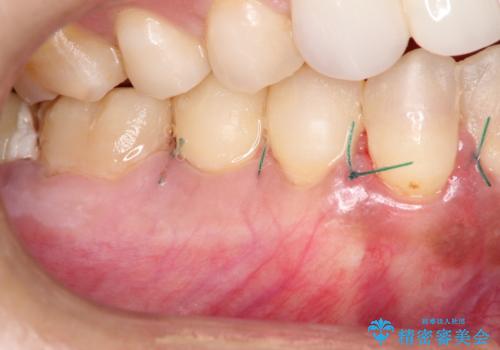

- 昔に受けた矯正治療がきっかけで歯肉が下がってしまった事を主訴として来院された患者様です。

結合組織移植術を行う方法を提案しましたが、傷口が口蓋にもできるのが嫌だとのことで、代替案としてバイオマテリアルを併用した根面被覆術を計画致しました。

治療対象部位は右下4,5,6番の3本です。

幸いなことに術後の痛みがほとんどなく、翌日には痛み止めも飲まずに済んだとのことでした。

治癒経過も良好で、患者様も満足されていました。また、知覚過敏も減ったとの事でした。